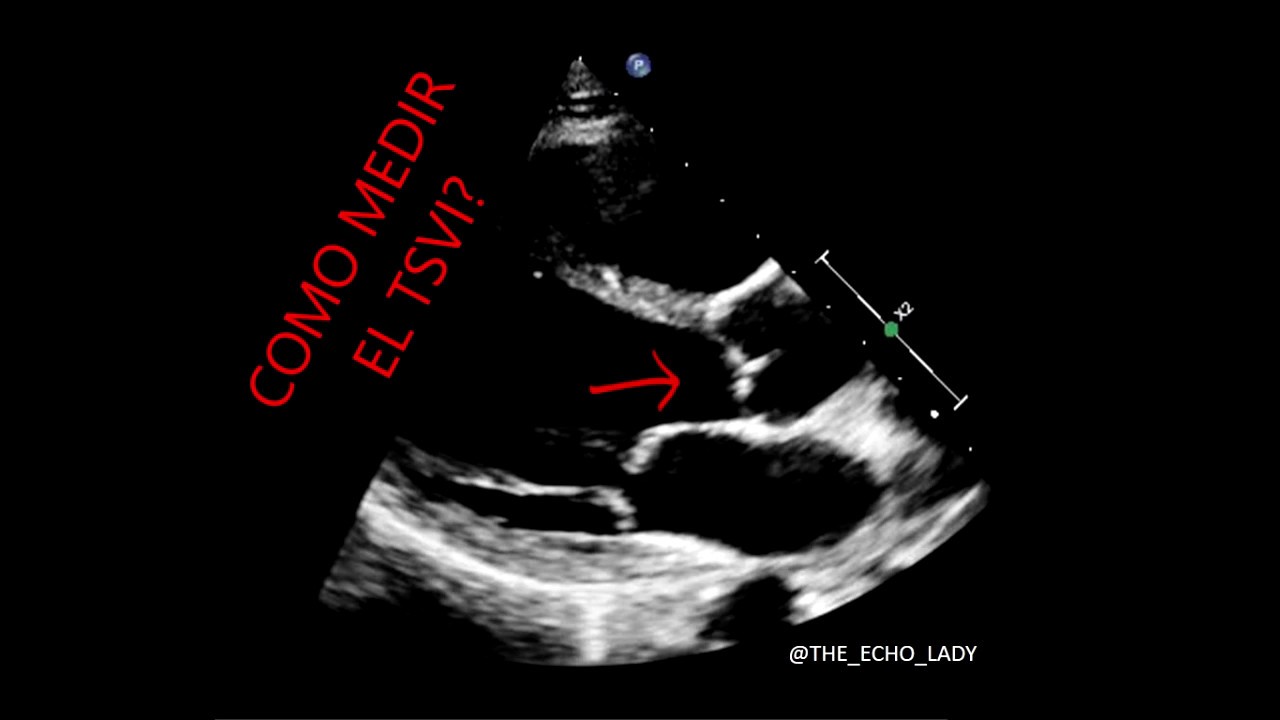

ECOCARDIOGRAMA Como medir el TSVI? YouTube Tapse En Ecocardiograma Se mide con ecocardiografía en modo m. El tapse y la fracción de. 142 rows medimos el tapse en los registros de modo m de la proyección de cuatro cámaras orientada en ecocardiografía bidimensional,. 📢 descubre cómo medir el tapse en ecocardiografía de manera efectiva con nuestra guía. Este análisis requiere una combinación de parámetros cuantitativos y cualitativos. 142 rows. Tapse En Ecocardiograma.